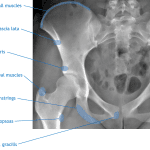

- Learn the major muscle and muscle group attachments on the anatomic pelvis (refer to first annotated image below)